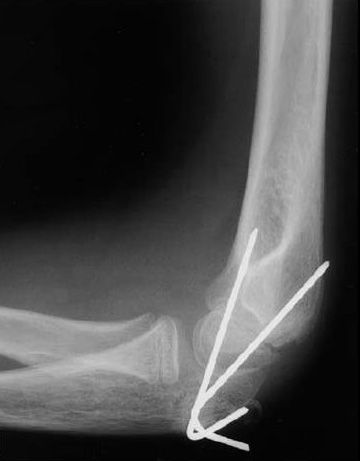

If bone fragments cut through the skin, a operation will be required to thoroughly clean the area and to fix the fracture. For some, full healing can take up to a year after injury. Arthritis literally means joint inflammation. Bone grafting involves placing additional bone around the area of the nonunion. The bone may take longer to heal if you suffer from diabetes or if you smoke. Casting extends above the elbow and down to the wrist, leaving the fingers free and the arm placed in a sling. How long does bone healing take? Open reduction and internal fixation (orif) is a type of surgery used to stabilize and heal a broken bone. Whether you have gone through surgery or gotten a simple splint, this amount of time is usually enough for your bones to heal and for you to start using your elbow normally. Use an ice pack, or put crushed ice in a plastic bag. We will do all we can to help your child emerge stronger. If you have fracture that doesn't require surgery, you'll need to wear a sling for two to six weeks. It is quite common to still experience some mild loss of mobility after this time, so it is very important to continue the range of motion and strength exercises that you learned in physical therapy.